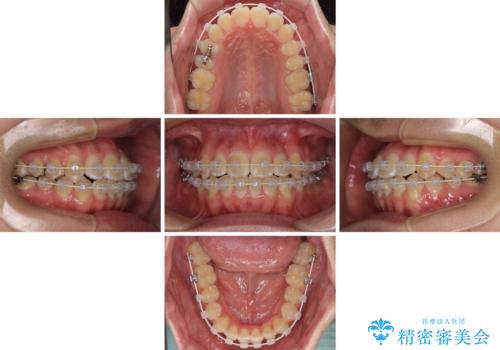

- 上下前歯のデコボコを気にして来院された患者様です。

ワイヤー矯正でもマウスピース矯正でも可能でしたが、短期間で、自身の手を煩わせることなく治療を行いたいとのことで、ワイヤー装置にて矯正治療を行うこととしました。

当初予定通り、1年間で治療を終えることができました。